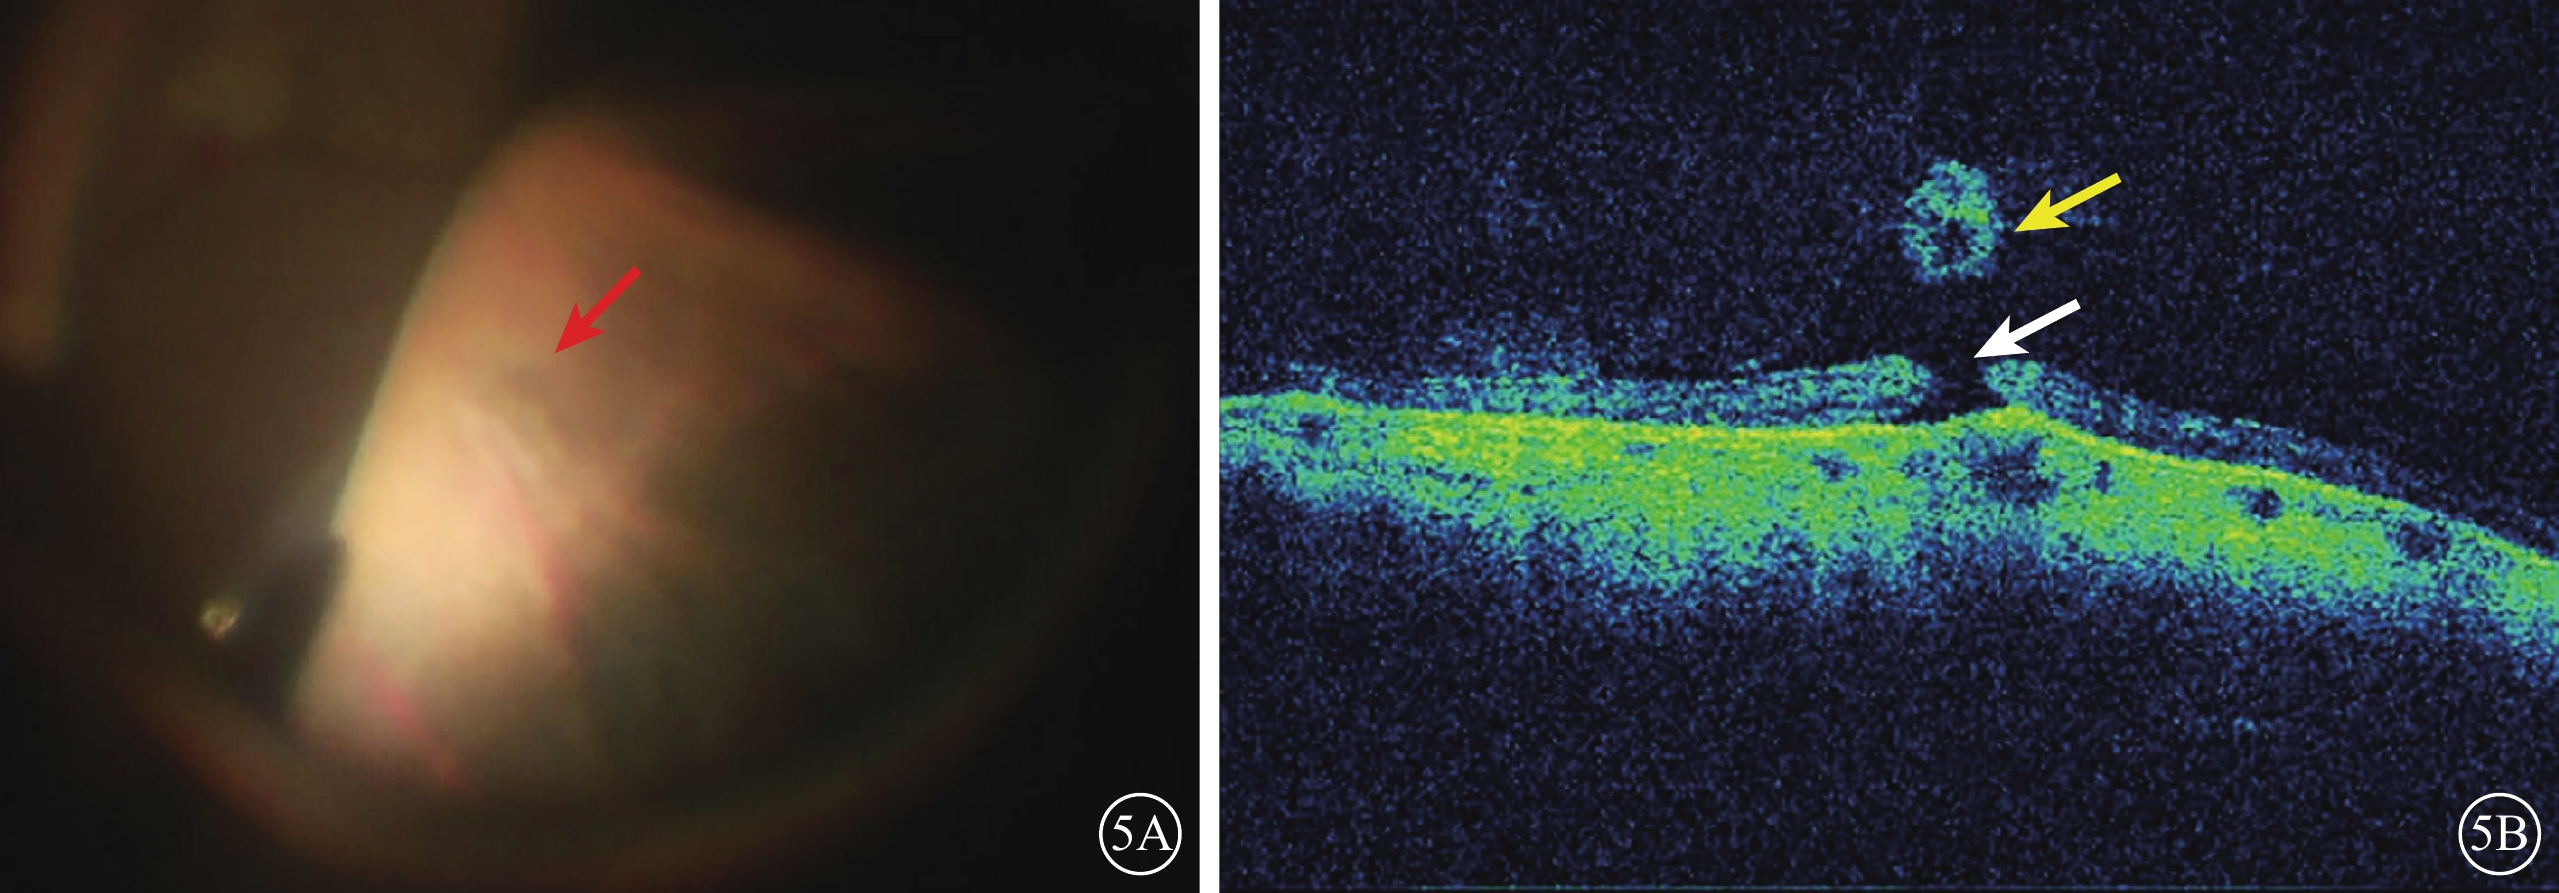

周邊視網膜細小裂孔,手術者顯微鏡下未查見明顯異常(圖5A),iOCT下局部視網膜連續性中斷及視網膜表面的游離組織瓣(圖5B)。